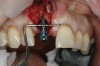

A 56-year-old female patient was referred for the evaluation of tooth No. 8 (Figure 4 and Figure 5). A periapical radiograph indicated that the tooth had undergone apicoectomy and received an excessively long post (Figure 6), and a cone-beam computed tomography (CBCT) scan of the site revealed a lack of buccal plate bone (Figure 7).

4. Facial and occlusal views of initial clinical presentation of tooth No. 8.

Figure 4